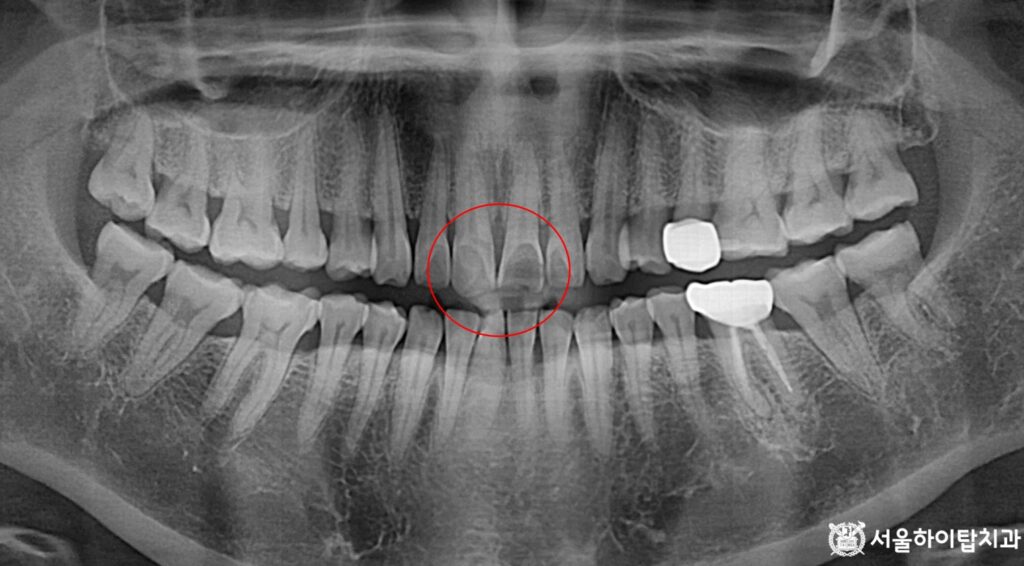

Panoramic X-ray – 파절이 의심되는 모습

먼저 엑스레이 사진을 통해 전반적인 구강 상태를 살펴보면,

현재 눈에 띄는 큰 이상 소견은 관찰되지 않습니다.

치아 배열이나 치조골 흡수, 충치·염증, 과거 치료 이력 등

일부 확인되는 요소들은 있으나 부평 치과 에서는

치료가 시급할 정도의 문제는 아닌 상태로 보입니다.

다만 술자의 관점에서 볼 때, 위턱(상악) 중앙 전치부에서

정상 치아 형태와는 다른 파절 소견이 확인됩니다.

이러한 변화는 엑스레이만으로는 한계가 있어,

구강 내 사진을 통해 실제 형태와 손상 범위를

보다 정확히 확인하는 과정이 필요합니다.